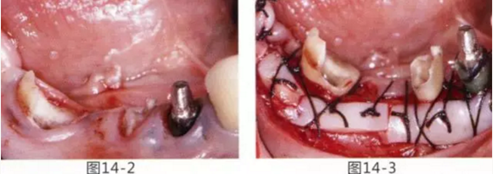

圖14-1 修復體周圍角化牙齦較少,很難進行清潔的狀態(tài),并有緣下齲壞的發(fā)生。

圖14-2,3 徹底去除齲壞后,試圖通過游離齦移植獲取生物學寬度和附著齦。

圖14-4~6修復體周圍角化牙齦較少,很難進行清潔的狀態(tài),并有緣下齲壞的發(fā)生。

圖14-7 配戴最終修復體完成5年后的狀態(tài)。保持良好。